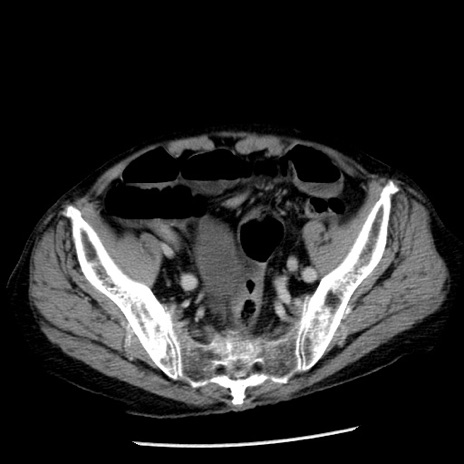

症例26(横断像)

【症例】80歳代男性

【主訴】嘔吐

【現病歴】昨晩2回嘔吐あり、今朝になっても嘔吐あり。来院。

【既往歴】胃潰瘍

【身体所見】意識清明、BT 37.6℃、BP 166/95mmHg、HR 100bpm、SpO2 97%、腹部:平坦・軟、腸蠕動音聴取良好、圧痛なし。

【データ】WBC 21900、CRP 1.46